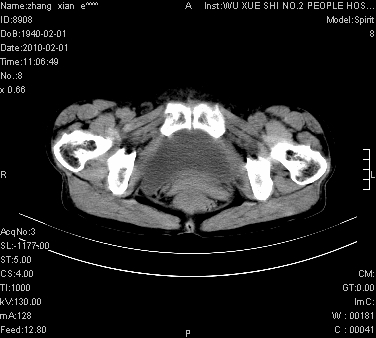

大量腹水,脾脏囊性占位,子宫颈占位,右侧腹股沟淋巴结肿大,建议+c,先查妇科。

腹盆腔大量积液,子宫增大,子宫颈增大外形不规则,内见低密度影,膀胱后壁显示不清,右腹股沟肿大淋巴结,脾脏囊性占位,子宫颈占位,子宫颈癌?建议增强。

腹盆腔大量积液,子宫增大,子宫颈增大外形不规则,内见低密度影,膀胱后壁显示不清,右腹股沟肿大淋巴结,脾脏囊性占位,子宫颈占位,子宫颈癌?建议增强。支持!